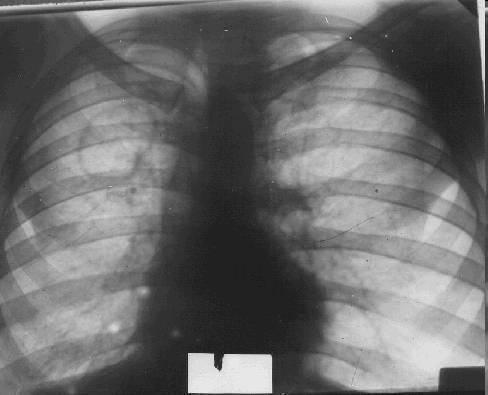

Диссеминированный (милиарный) туберкулез

На представленной рентгенограмме (позитив) четко визуализируются многочисленные небольшие очаги с четкой границей, не сливающиеся друг с другом, средней интенсивности, диаметром 2-3 мм, приблизительно равномерно расположенные в области обоих легочных полей. Сосудистый рисунок легкого оценить невозможно из-за визуального наложения очагов.